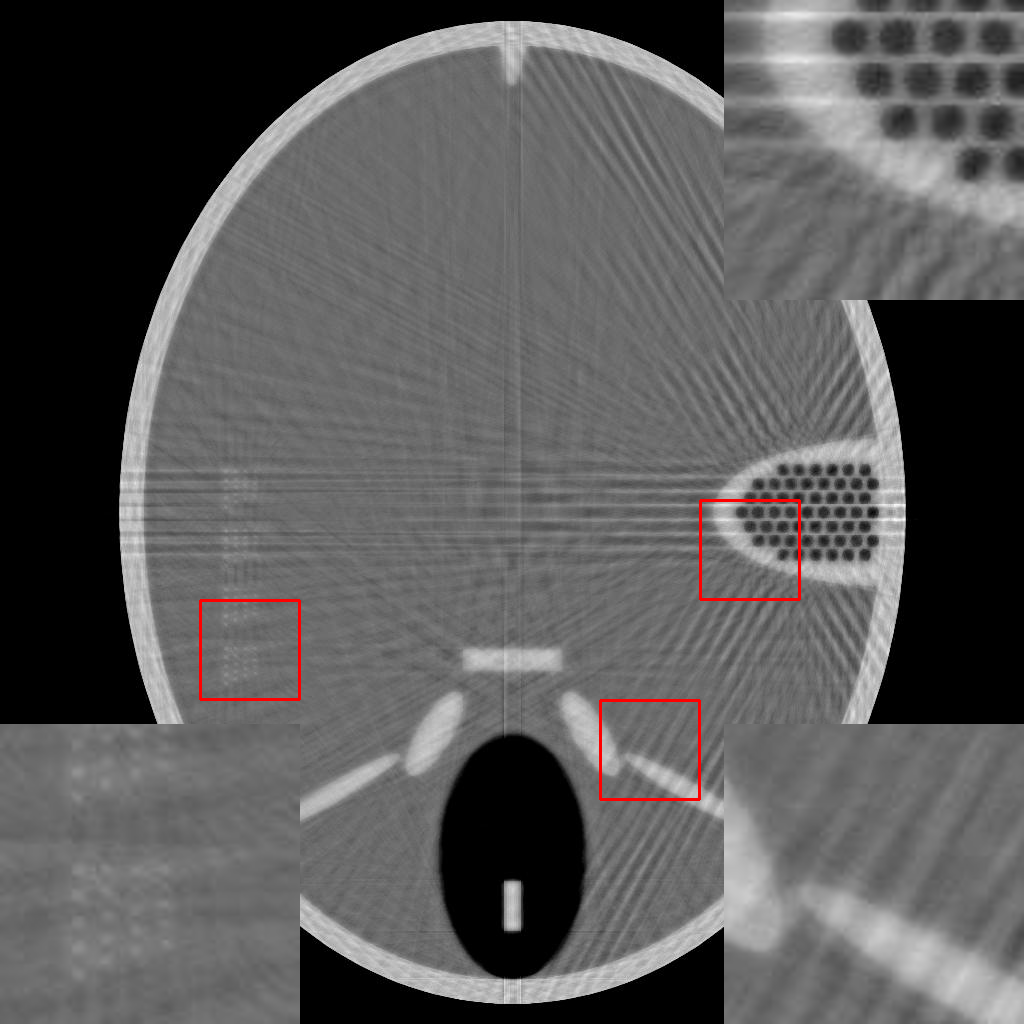

For a more direct comparison, the three aforementioned methods are tested on the Forbild phantom under few-view ( views, uniformly distributed from to ), and limited-angle ( views, uniformly distributed from to ). From Fig.3, it is clear that both the DIP and RBP-DIP exhibit superior performance compared to ASD-POCS, particularly in the reconstruction of detailed structures. The magnified views of these structures are available in the bottom left and top right corners of these images. In contrast to DIP, RBP-DIP is better at mitigating some neural network-specific artifacts, with the corresponding magnified view presented in the bottom right corner of these images.

It is worth mentioning that another significant factor contributing to the substantial advantage of DIP and RBP-DIP over ASD-POCS is the piece-wise constant nature of the Forbild phantom. Therefore, to better assess the performance of the proposed method in practical applications, multiple experiments using real CT images are conducted in the following sections.